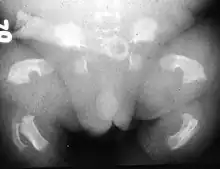

O Tipo 1 caracteriza-se por rizomelia extrema. A nível craniano, a base do occipital apresenta uma dimensão reduzida, incluindo o foramen magnum, testa proeminente e hipertelorismo ocular (afastamento amplificado das cavidades orbitais). No tórax ocorre platispondilia vertebral (achatamento dos corpos vertebrais) e as costelas apresentam encurtamento com extremidades metafisárias em forma de “chávena”, características que lhe conferem uma configuração mais estreita e em forma de triângulo. Na cintura pélvica, o ílion apresenta uma dimensão mais curta com a margem inferior horizontal, e o ísquion e a púbis possuem uma fisionomia mais larga e curta. Os membros superiores e inferiores caracterizam-se por ossos longos arqueados com diminuição muito significativa do comprimento e com metáfises alargadas. O fémur destaca-se pela sua aparência semelhante a um “auscultador de telefone”. Os membros superiores por vezes podem apresentam dígitos encurtados, verificando-se por vezes sinostose rádio-cubital.[4][6]

O Tipo 2 corresponde a uma manifestação menos severa e mais rara. A alteração mais distintiva observa-se a nível craniano, pela sua forma de “folha de trevo” devido à craniossinostose/oxicefalia (encerramento prematuro da sutura coronal). Os ossos longos apresentam encurtamento, mas uma forma retilínea ao invés de arqueada.[2][3][9][10]